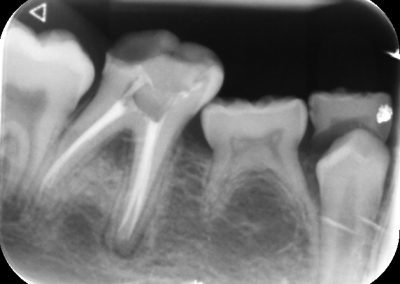

During the consultation, the dentist will first listen to your concerns and carry out appropriate tests to identify the right tooth that is causing pain. As a part of the diagnosis, your dentist will carry out various clinical tests to identify the right tooth and will take some radiographs which can aid in the diagnosis.

An access cavity is placed on the surface where the patient bites, to reach the root canals of the tooth. Once all the canals are identified, small files are used to remove the infected pulp.

Files of different sizes are used to eliminate bacteria and infection and to shape the canals. The canals are disinfected thoroughly with irrigants and later the canals will be sealed in 3 dimensions with a special medicament called gutta-percha to prevent reinfection of the tooth and the access cavity will be sealed with a temporary filling.